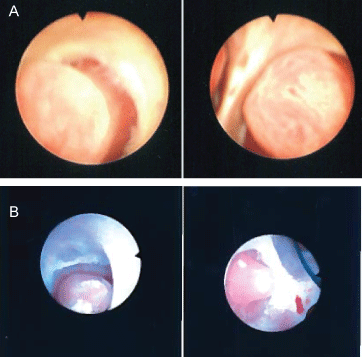

The patient underwent cystoscopy with bilateral retrograde pyelogram that revealed efflux of bloody urine from the left ureteral orifice, and filling defects in the left renal pelvic and lower pole calyx (Figure 1). The ureter was stented with a double J stent and subsequent ureteroscopy was performed. The patient was found to have renal papillae which were significantly hypertrophied and highly vascularized (Figure 2). The papilla of the lower pole calyx was hypertrophic to the point of protrusion into the renal pelvis. These hypertrophied lesions were biopsied and then ablated with a holmium laser. Pathology revealed benign fragments of renal medulla with tubular calcifications. MR angiogram performed one month later showed no vascular lesions or malformations. MR urogram showed prominent medullary pyramids in bilateral upper poles, consistent with renal papillary hypertrophy (Figure 3). The patient was followed without recurrence of hematuria for over 9 months.

Figure 1a: Left retrograde pyelogram demonstrating filling defects in renal pelvis, lower pole and mid pole calyces. Case 1-EC.

Figure 1b: Left retrograde pyelogram demonstrating filling defect in left upper pole and mid pole calyces. Case 2-AS. View Figure 1

Figure 2a: Hypertrophied papilla of the left mid pole and lower pole calyx. Case 1-EC.

Figure 2b: Hypertrophied papilla of the left upper pole calyx. Case 2-AS. View Figure 2

Patient underwent cystoscopy with retrograde pyelogram that revealed a filling defect in the upper pole calyx of the left kidney, but no lesion in the bladder or contralateral kidney (Figure 1b). A double J stent was placed with delayed ureteroscopy. On ureteroscopy, all the calyces of the left kidney were congested, enlarged, and demonstrated hypertrophic papilla (Figure 2b). Active oozing of blood was seen from the papillae in the upper pole calyx, which was ablated with a holmium laser. Patient was free of hematuria on follow-up for one month. She had recurrence of hematuria with MRI and MR urogram negative for pathology other than bilateral papillary hypertrophy. Patient's symptom of hematuria resolved and she is asymptomatic for 9 months.